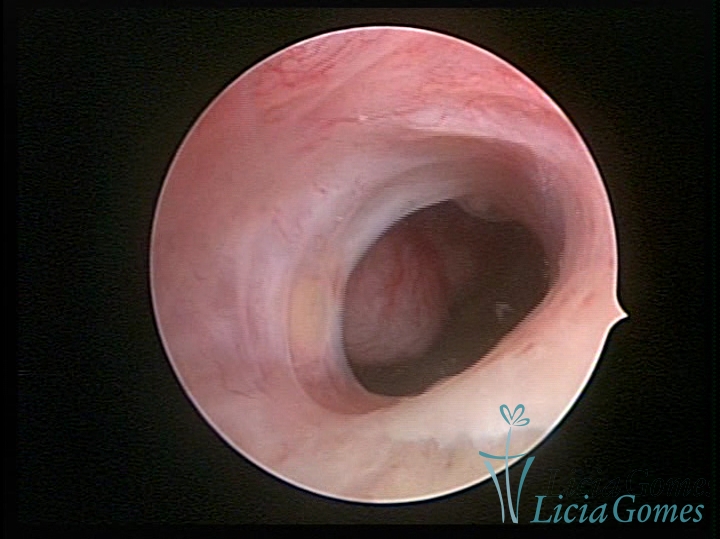

SINÉQUIA TIPO MUCOSA